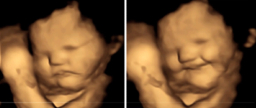

子宮嬰兒有沒有生命?3D超聲波圖片揭開秘密